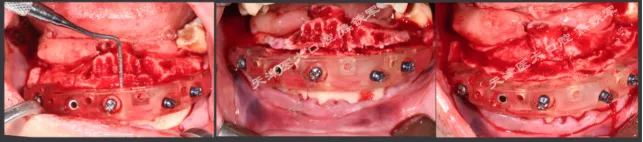

下颌即刻种植即刻修复手术过程

· 下颌士卓曼360数字化序列导板+预成临时修复体

· 翻瓣,利用松牙固定后的余留牙支持连接在一起的牙支持导板和基部导板,使骨支持的基部导板就位于骨面。

· 并用固位钉固定,拆除牙支持式导板,拔除余留牙。

· 基部导板上缘做为截骨线,精确去骨,平整骨面。

· 全程植入导板就位于基部导板上,固位钉固定,引导种植体植入。

· 种植体植入后,安装复合基台基底

· 临时修复体就位于基部导板,固位钉固定,口内Pick-up后取下修改,戴回口内,咬合关系良好。